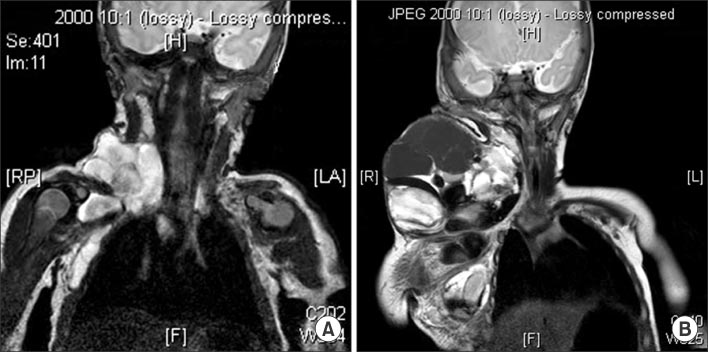

Fig. 5

(A) Sagittal T2-weighted MRI shows cervical lymphangioma which are infiltrating tongue base (patient No. 11). (B) Decreased lymphatic malformation after surgery.

Fig. 5 (A) Sagittal T2-weighted MRI shows cervical lymphangioma which are infiltrating tongue base (patient No. 11). (B) Decreased lymphatic malformation after surgery.